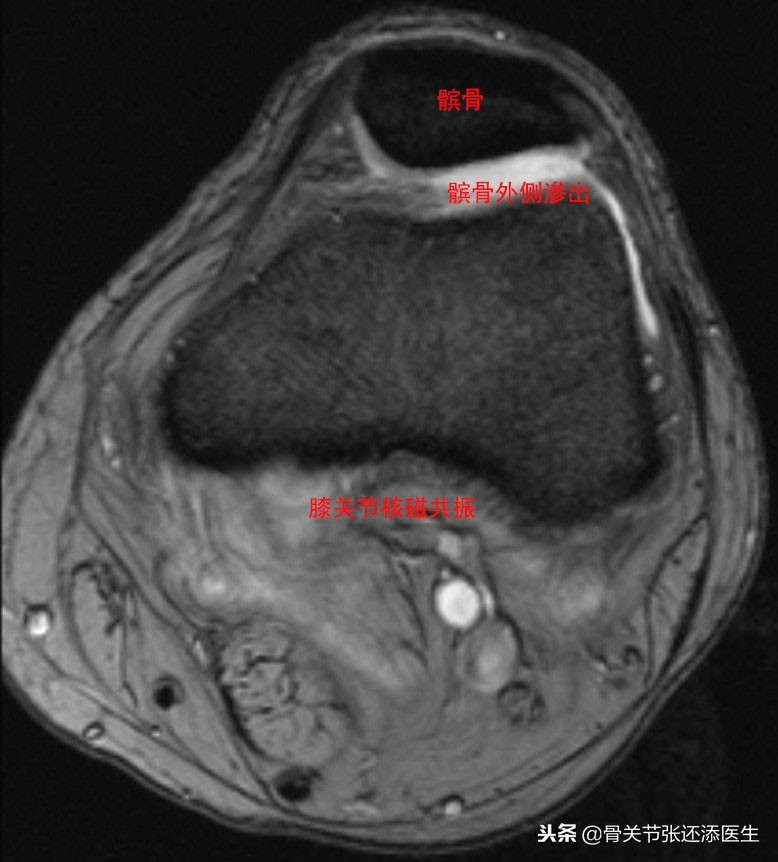

3.MRI有髌骨损伤及水肿变现

MRI显示髌骨外侧软骨磨损半水肿